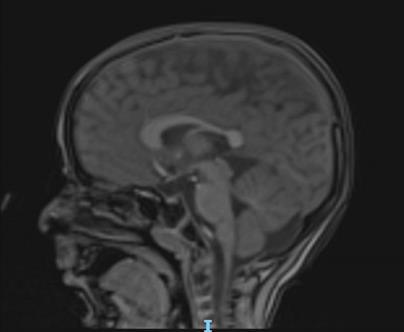

- Imaging: Periventricular leukomalacia, thinning of the corpus callosum

- Diagnosis: Spastic diplegia secondary to cerebral palsy RM 1/10/2019

01/22 NHC Admission for Preoperative Assessment

Brain and spinal cord MRI under general anesthesia